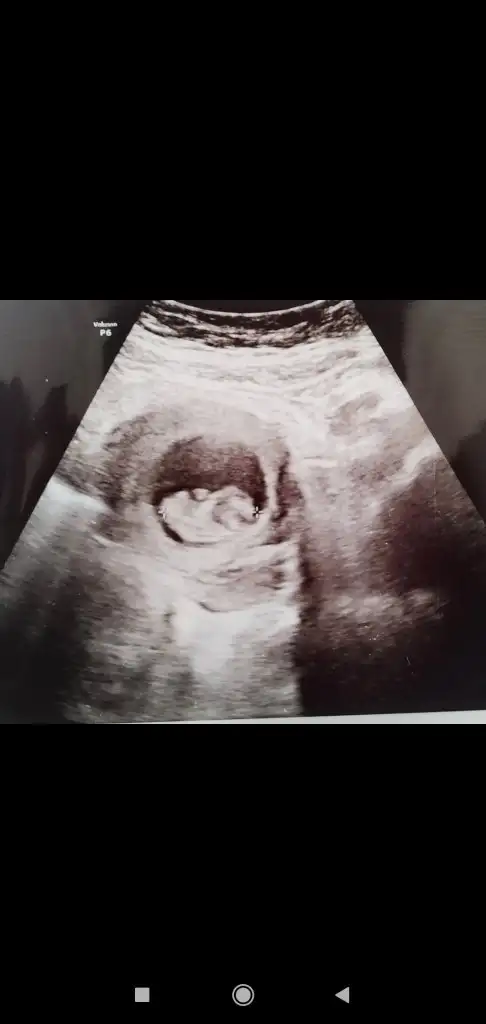

Ay ne güzel başlık banada tahmın edebılır mısın😊🤗 burda 8 haftalık karından bakıldı sımdı 10 haftalıgım 2 hafta sonra gidicem doktora bır tahmınde bulınabılır mısın

• IMG-20220414-WA0006.webp

IMG-20220414-WA0006.webp

23,5 KB · Görüntüleme: 92

Bu arada bende tatlı asla yıyemıyorum mıde bulantılarım var kıloda verdım

Burada 8 haftalık karından canım